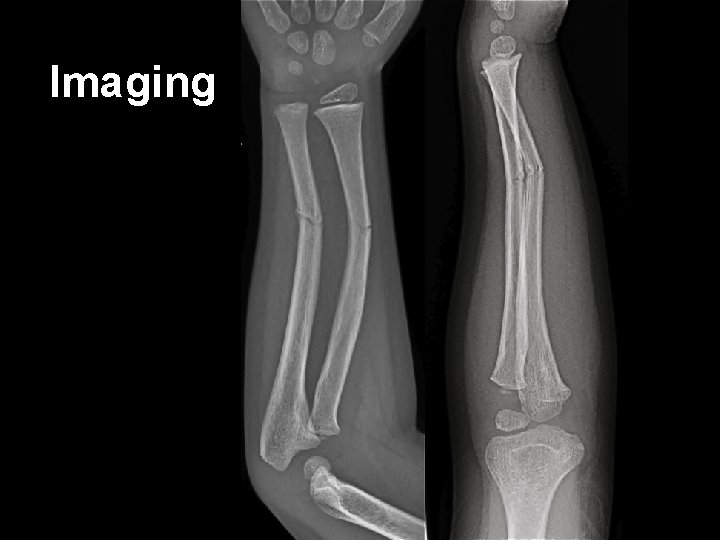

Case • An 8 year old boy – Monkey bars + Gravity • FALL – Obvious left upper limb deformity – Note • • Past History Last intake of solids / liquids Assessment of injury – neurovascular observations Pain score and management

Imaging

Case • An 8 year old boy – Monkey bars + Gravity • FALL – Obvious left upper limb deformity – Note • Past History • Last intake of solids / liquids • Assessment of injury – neurovascular observations • Pain score and management

Ketamine: The procedure • 8 year old boy with forearm fracture – Weight – 25 kg • Remember topical anaesthetic for IV insertion • Guided imagery; music • Must prepare all equipment for reduction and plaster as per local guidelines – May include: Image Intensifier (+ radiographer), plaster of Paris, padding, sling etc • Consent for sedation AND for procedure – Explain risks